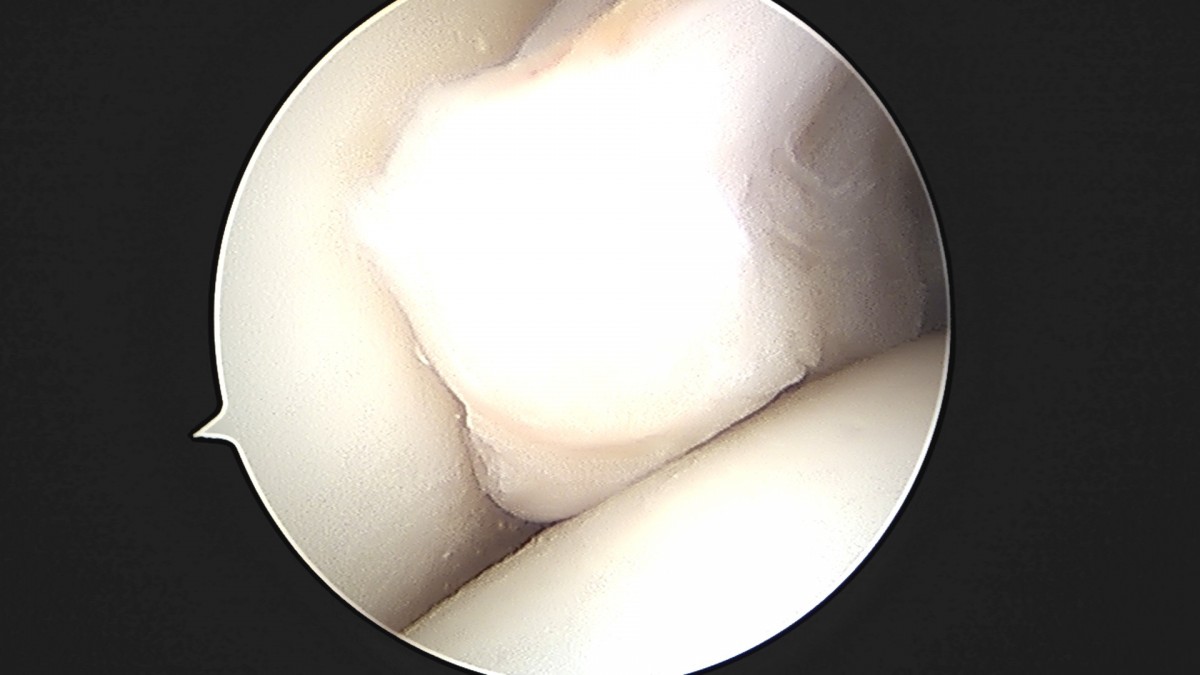

이재상원장님 발목 활액막 절제술 및 인대 봉합술 정보O 환자

dae765e4d9ac96aee867c9d6292d8784_1758003799_5379.jpg